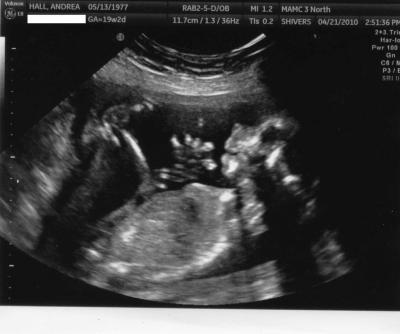

Hier noch mal ein Bild, wo sie total relaxed daliegt mit den Fuessen fast ueberm Kopf

Bild zu